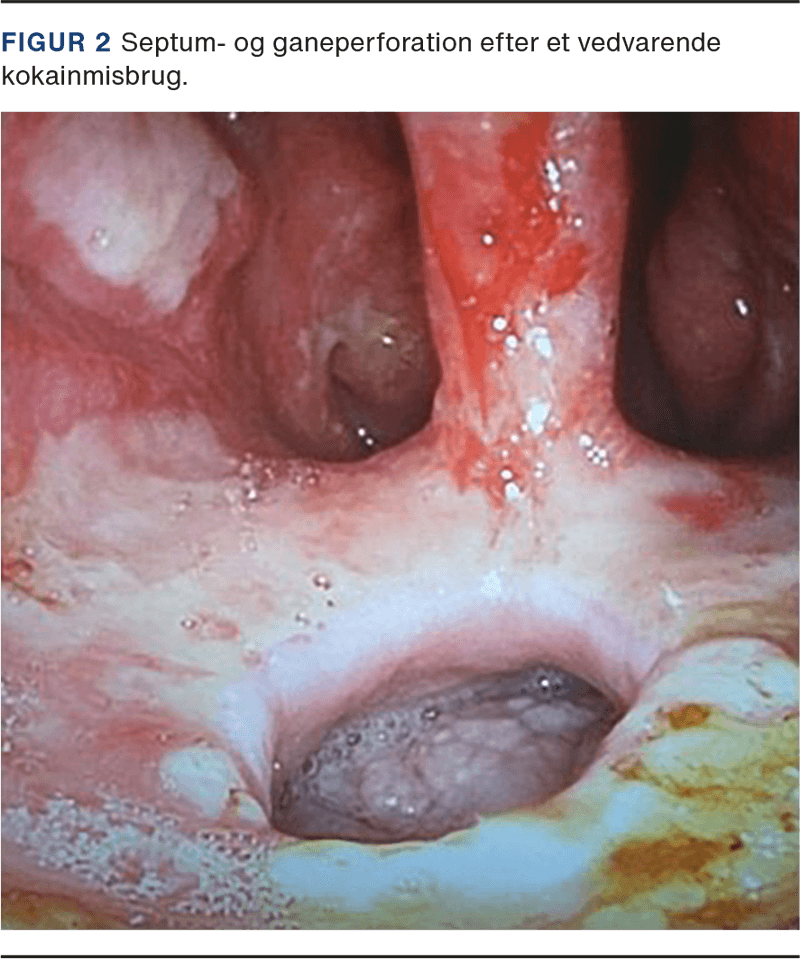

Det er uvist, hvor hurtigt CIMDL udvikles, men der er observeret septumperforationer hos misbrugere, som har haft et misbrug i alt fra 2 år og op til 30 år og indtaget doser lige fra 1 til 180 g/uge [12, 13]. Der mangler stadig longitudinale followupstudier, som kan hjælpe med at bestemme sammenhængen og korrelationen mellem mængden af kokain forbrugt over tid og udbredelsen af vævsdestruktion (Figur 2 og Figur 3).

Patienter med CIMDL henvender sig typisk med en eller flere af følgende symptomer: skorpedannelse, smerter, en »fløjtende« nasal respirationslyd, sammenfald af ydre næse, dvs. saddelnæse, nasalstenose, næseblod, manglende lugtesans, dårlig ånde, nasal tale, fejlsynkning. Kliniske fund omfatter ud over perforation af næseskillevæggen, diffuse nekrotiserende læsioner, skorpedannelser og bakterielle superinfektioner [10-12]. Der kan også forekomme sår i og omkring næsen, f.eks. ved overlæben, columella, ala nasi og på svælgets bagvæg. I svære tilfælde ses der involvering af den hårde del af ganen, næsemuslingerne, de mediale vægge af sinus maxillaris og ethmoidet. Selv destruktion af orbitas gulv, os sphenoidale og ductus nasolacrimalis er beskrevet kasuistisk [8, 9, 11, 13].